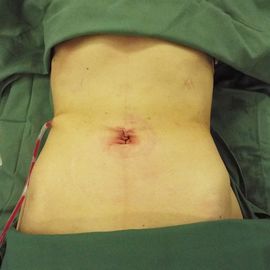

術後創部画像